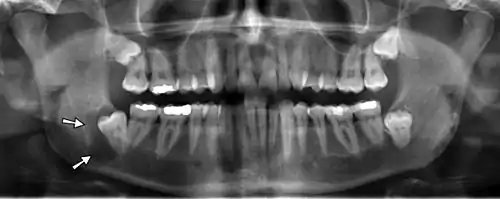

Most cysts are discovered as a chance finding on routine dental radiography.[7] They are often asymptomatic unless there has been long-standing with significant enlargement (causing bony expansion or egg-shell cracking feeling[7]) or secondary infection.

On an x-ray, cysts appear as radiolucent (dark) areas with radiopaque (white) borders.[7] However, cysts in maxillary sinus, also known as antrum, can appear radiopaque as the surrounding air absorbs fewer photons than the cystic fluid content.